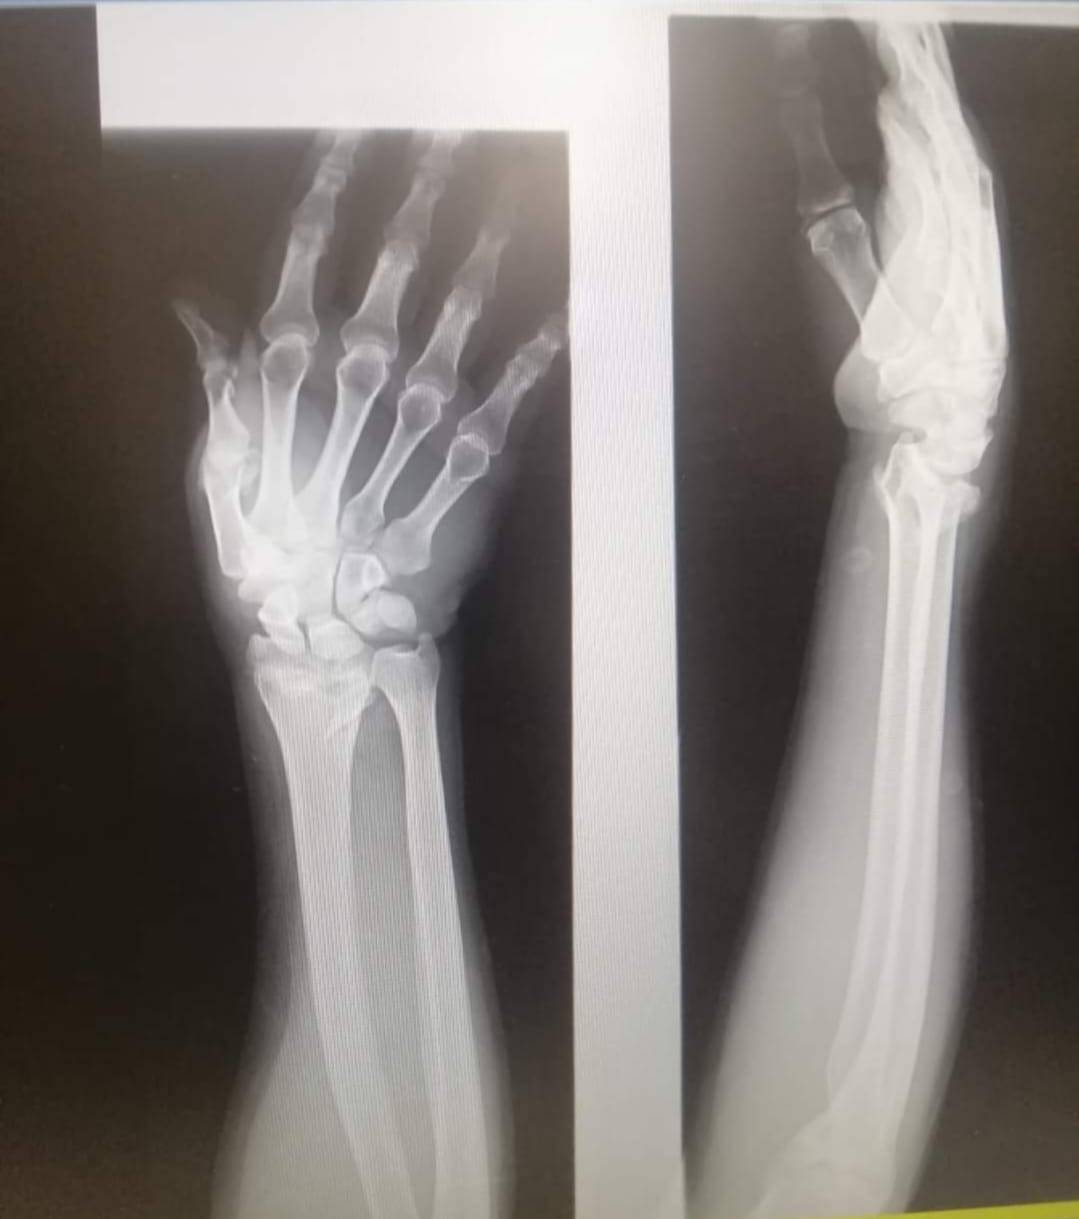

وطنا اليوم -  يقوم بعمليات تثبيت الكسور المعقدة بشكل طاريء وتبديل المفاصل بشكل مبرمج  مما خفف على المواطنين البحث عن أسرة في مستشفيات مركزية رغم صعوبة عمليات العظام من الناحية التقنية في المستشفيات النائية  إضافة الى  استقبال اعداد كبيرة بالعيادات ومعالجة جميع المرضى بالطرق المثلى انه الدكتور الانسان البارع والمتميز يزيد البريزات طبيب العظام في مستشفى الاميرة سلمى / ذيبان عيادة العظام  علماً بأنه كان  مستشفى تحويلي منذ تاسيسه والدكتور البربزات وقبل اربع سنوات في عام 2020  منذ انتقاله للمستشفى يقوم بهذه العمليات ومن بينها  عمليات نوعية لمرضى يعانون من كسور معقدة في الترقوة واجراء عمليات دقيقة ومعقدة لكسور لمرضى في مختلف أنحاء الجسم وعمليات تثبيت الكسور المعقدة وتركيب المفاصل وغيرها الكثير  والديسك " وآلامه وتبعاته وعلاجه وإجراء عمليات معقده وصعبه.

وأجرى الدكتور البريزات عمليات كبرى في جراحة العظام والتي تحتاج إلى مراكز متقدمة ومتطورة. وكذلك العمل على تثبيت أغلب انواع الكسور بطريقة طارئة وتبديل المفاصل بطريقة مبرمجة بما يتناسب مع امكانات المستشفى والتي هي  جزء من  العمليات الدورية بمستشفى الاميرة سلمى في ذيبان  والتي تخفف العبئ على المستشفيات المركزية وعلى المواطن في آن واحد.

وعبر كثير من  المرضى وذويهم عن عظيم شكر هم وامتنانهم للدكتور البريزات على ما بذله ويبذله  من جهود كبيرة واستثنائية في تعامله مع المرضى والمراجعين  ومتابعته الحثيثة لهم والاطمئنان عليهم والتي تكللت جميعها بالنجاح وله الدور الكبير   برفع كفاءة قسم العظام  بالمستشفى بشكل عام والذي  أصبح  متطوراً بالقيام بالعمليات مثل تثبيت الكسور المعقدة و تركيب المفاصل و غيرها.